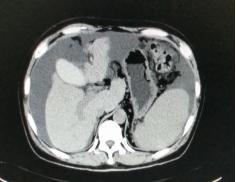

我们将这种方法应用到150 多例没有艾滋病病毒感染的一般肝硬化患者,结果收到更好疗效[19-20]。例如1例患者男,56 岁,失代偿肝硬化大量腹水合并脐疝(图1)。 CT检查提示肝脏明显萎缩,肝脏体积1302 ml,大量腹水, 脾脏肿大(图2)。我们对患者进行脾切除加脐疝修补,自体骨髓经门静脉输注治疗。手术后3 个月,肝功能Child-Pugh分级从C级转成*级A**,手术后1 年,肝功能正常,腹部伤口愈合良好(图3)。CT检查提示肝脏明显增大,体积1796 ml,腹水基本消失(图4)。对于肝功能C级的患者手术风险比较高,围手术期输注白蛋白,凝血酶原复合物,纤维蛋白原,改善肝脏功能,手术中经胃网膜右静脉插管埋置骨髓输注装置,输注自体骨髓。随着自体骨髓干细胞在肝内发生复杂的变化,肝硬化组织中的胶原纤维被降解和吸收,肝脏组织的增生和体积增大,肝功能好转,门静脉压力会逐渐降低。但是在手术和自体骨髓经门静脉输注后1到2 年内,仍然有可能随时发生上消化道出血,需要经胃镜检查,套扎食管黏膜下明显曲张的静脉血管。这样脾脏切除解除脾功能亢进,不做贲门周围血管离断,减少了手术损伤。食管黏膜下静脉曲张用胃镜下套扎治疗。待肝硬化的逐渐逆转,食管黏膜下静脉曲张程度将会逐渐减轻。

图2.术前腹部CT断层照片

图4.1年后对比手术前同一部位CT断层照片